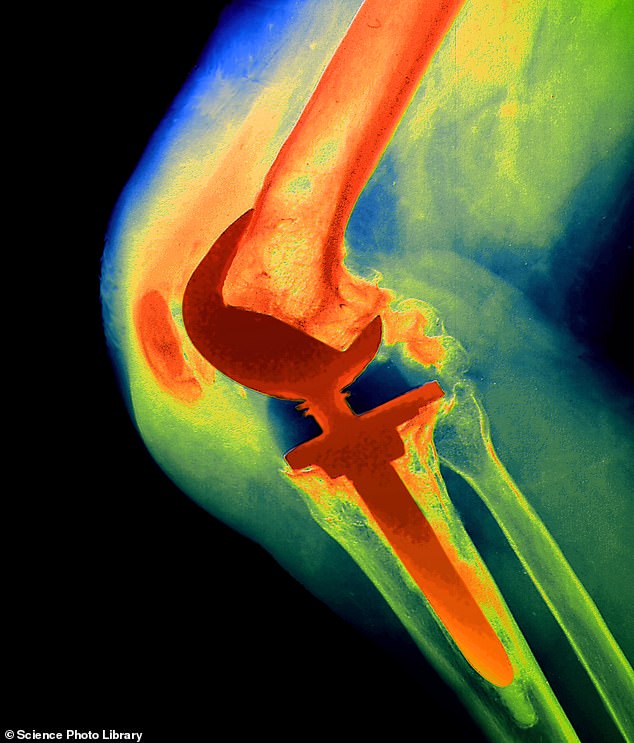

The NexGen implant was used for a total knee replacement, which involves having the lower end of the thigh bone and the upper end of the shin bone replaced with metal and plastic parts.

The prosthetic was withdrawn from the UK market in December 2022 by the US manufacturer, Zimmer Biomet, after the implant was linked to higher revision rates. Studies also revealed that hundreds of patients had been left in constant agony because a component (the NexGen stemmed option tibial component) was coming loose, leaving metal rubbing on bone.

But it appears to have differed in one key aspect – it lacked a coating which was a feature of previous NexGen products. This coating was on a part known as the tibial tray, which is in contact with the top of the shin bone and cemented into place.

‘This coating helps the implant bond to bones in the leg – in much the same way as the rough surface on bricks in a wall help them to fix to the surrounding cement properly,’ explains Professor David Barrett, a consultant knee surgeon at Southampton University Hospital.

Without this, the implant was in some cases able to move more than it should, he adds.